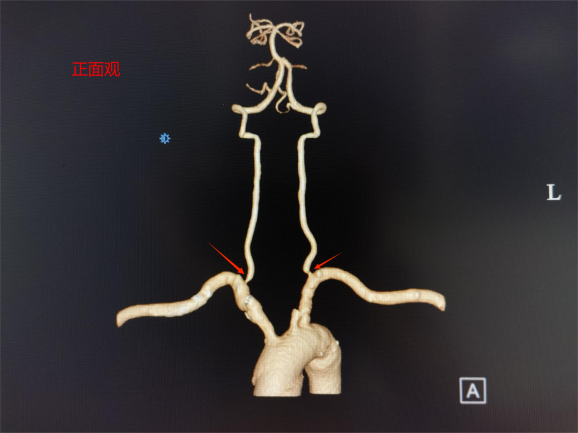

家住桂林的王大叔近半年来反复出现头晕、头疼,并伴有感觉脚踩棉花、行走不稳的症状,这些症状给他带来了极大的困扰,严重影响了他的日常生活。在家人陪伴下王大叔来到中南大学湘雅二医院桂林医院就诊,经过专业医疗检查,医生发现其双侧椎动脉起始段存在重度狭窄。椎动脉是向脑部供血的重要血管之一,如果它严重狭窄就会导致大脑的血液供应减少(后循环缺血),从而引发上述症状。

桂林医院血管外科舒畅教授团队经过仔细评估,决定采用微创腔内治疗,植入椎动脉支架进行治疗。右侧椎动脉微创血管重建手术具有创伤小、恢复快、效果显著等优点,是治疗血管狭窄的常用手段之一。